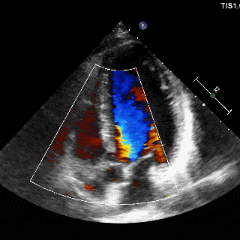

术前超声

超声提示:主动脉瓣右冠瓣脱垂,主动脉瓣中-重度关闭不全,左心系统扩大,二尖瓣少量反流。

术后超声可见反流消失,血流动力学正常